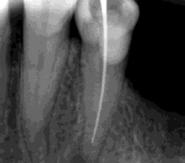

Las Figuras 16 y 17 muestran el tratamiento endodóntico del incisivo central superior izquierdo. Las Figuras 18 y 19 muestran el tratamiento endodóntico del incisivo central superior derecho. Se puede observar que también se realizó la endodoncia del resto radicular del incisivo central superior derecho pues no se debe realizar la exodoncia del mismo.

La Figura 20 muestra la imagen del carcinoma epidermoide de lengua antes de la radioterapia. Las Figuras 21,22 y 23 muestran las radiografías dentoalveolares del segundo premolar superior derecho con diagnóstico

de necrosis pulpar por radiación ionizante y el tratamiento endodóntico correspondiente.

Las Figuras 24 y 25 son las imágenes de las radiografías dentoalveolares del diente incisivo lateral inferior derecho y las Figuras 26 y 27 del incisivo lateral inferior izquierdo. Ambos dientes afectados de necrosis pulpar con lesiones periapicales por efecto de la radioterapia y los tratamientos endodónticos.